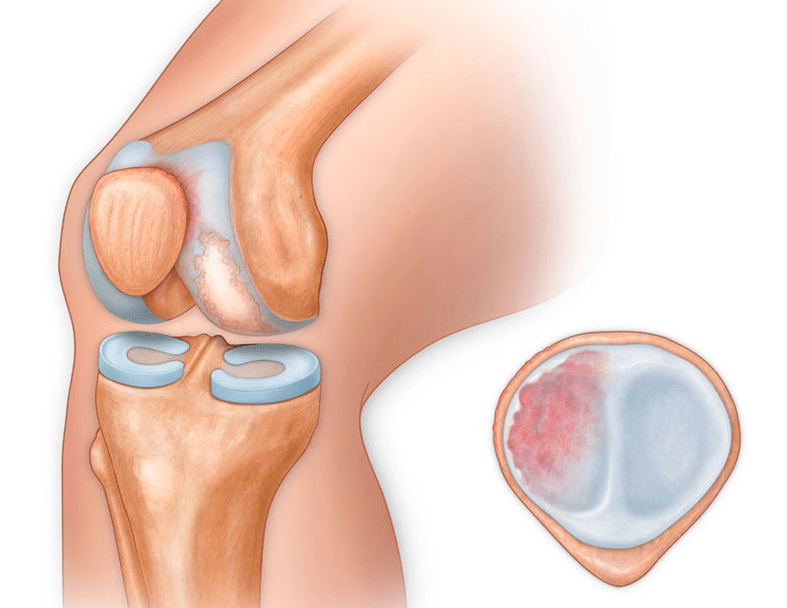

Αρθροπάθεια της άρθρωσης του γόνατος (γονάρθρωση) είναι μια προοδευτική χρόνια πάθηση των αρθρώσεων του γόνατος με βλάβη, λέπτυνση και καταστροφή του χόνδρινου τμήματος του (αρθρικές επιφάνειες μηριαίου οστού και κνήμης), καθώς και βλάβη στο υποχόνδριο οστό. Έχει αποδειχθεί με μελέτες (αρθροσκόπηση και μαγνητική τομογραφία) ότι εκτός από βλάβες στον αρθρικό χόνδρο εμπλέκονται στη διαδικασία οι μηνίσκοι και ο αρθρικός υμένας. Η γονάρθρωση είναι μια από τις πιο συχνές ορθοπεδικές παθολογίες. Υπάρχουν τα συνώνυμά του - οστεοαρθρίτιδα (ΟΑ), παραμορφωτική αρθροπάθεια. Η νόσος αποτελεί σημαντικό κοινωνικοοικονομικό πρόβλημα, καθώς είναι ευρέως διαδεδομένο και επιδεινώνει σημαντικά την ποιότητα ζωής των ασθενών λόγω του συνεχούς πόνου και, επιπλέον, γίνεται αιτία υψηλής αναπηρίας.

γονάρθρωση της άρθρωσης του γόνατος

Με την αρθροπάθεια (οστεοάρθρωση), εκτός από την προοδευτική καταστροφή του χόνδρου, την απώλεια της ελαστικότητάς του και τις ιδιότητες απορρόφησης κραδασμών, τα οστά εμπλέκονται σταδιακά στη διαδικασία. Υπό φορτίο, εμφανίζονται αιχμηρές άκρες (εξωστώσεις), οι οποίες λανθασμένα θεωρούνται «αποθέσεις αλατιού» - με την κλασική αρθροπάθεια, δεν εμφανίζεται εναπόθεση αλατιού. Καθώς η αρθροπάθεια εξελίσσεται, συνεχίζει να «τρώει» τον χόνδρο. Στη συνέχεια το οστό παραμορφώνεται, εκεί σχηματίζονται κύστεις, επηρεάζονται όλες οι δομές της άρθρωσης και το πόδι λυγίζει.

Εκτός από το εσωτερικό ή το εξωτερικό μέρος του γόνατος, η αρθροπάθεια μπορεί επίσης να επηρεάσει τις επιφάνειες μεταξύ της επιγονατίδας και της μεσοκονδυλικής αύλακας του μηριαίου οστού. Αυτή η επιλογή ονομάζεται επιγονατιδομηριαία αρθροπάθεια.